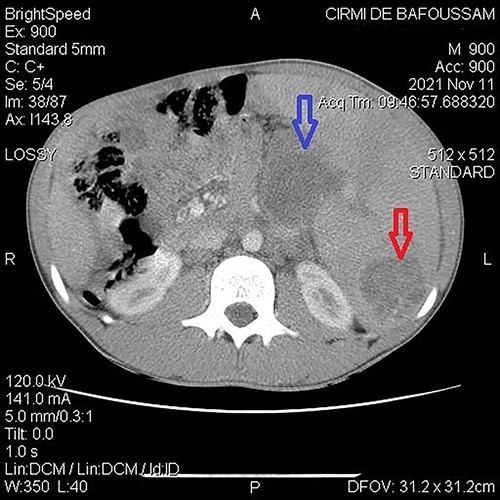

A 15-year-old patient presented with a 3-week history of left upper quadrant abdominal pain with no other symptoms. He had no prior history of pulmonary TB. His vital signs were as follows: temperature = 37°C, blood pressure = 120/78 mmHg, pulse = 84/min, respiratory rate = 15/min, SpO2 = 96% on room air; and physical examination only revealed a mild tenderness in the left upper quadrant with the tip of the spleen expanding to the umbilicus. An abdominal ultrasound (US) followed by a computed tomography (CT) scan revealed a heterogeneous splenomegaly with multiple cystic masses in the spleen and the tail of the pancreas (Figs 1 and 2). Laboratory exams showed a white cell count of 2600/mm3, hemoglobin of 11.4 g/dl, C-reactive protein (CRP) of 34 mg/l, hemoglobin electrophoresis AA and negative malaria and HIV tests. We suspected a primary or secondary malignancy of the spleen, like a lymphoma or a metastatic pancreatic carcinoma. The other diagnoses were tropical splenomegaly and splenic infarct. We performed a distal pancreatectomy with splenectomy, and histopathological analysis revealed caseating granulomas of the spleen (Fig. 3) with no malignancy suggesting TB. Further, a Ziehl-Neelsen stain of the specimen showed acid fast bacilli (AFB). The patient received anti-TB drugs, had an uneventful post-operative course and was discharged on post-operative day 7. On the first month follow-up visit, he reported marked improvement of his symptoms.

Abdominal CT demonstrating a cystic mass in tail of the pancreas (top arrow) and the tip of the spleen (bottom arrow).